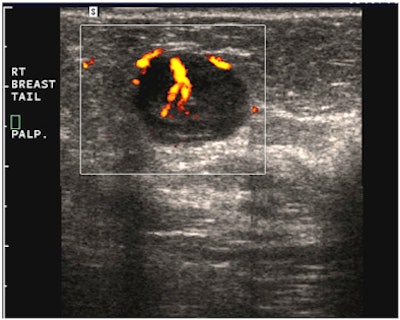

"A simple, yet powerful application of PDUS is differentiating between a rounded, markedly hypoechoic tumor and a [thickened] cyst with low-level internal echoes," he said. "The detection of the smallest vessel within the lesion automatically excludes a cyst -- or any other fluid collection -- and confirms a neoplasm. This very simple yet very useful application of PDUS is still underused."

| Images are of a circumscribed round pseudocystic mass. Above, grayscale US shows a cystic appearing mass with some low-level internal echoes. Below, PDUS performed with only minimal pressure applied through the probe shows internal vascularity, thereby excluding a fluid-filled lesion and confirming a tissular mass. Fine-needle aspiration readily confirmed a metastasis from a uterine leiomyosarcoma treated six years previously. All images courtesy of Dr. Bruno Fornage. |